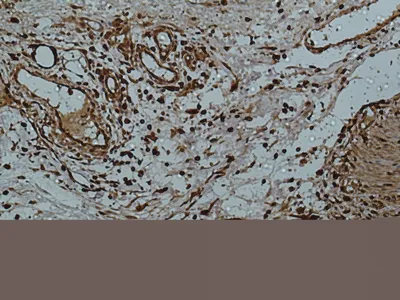

Collagen III(Q76)Mouse Monoclonal Antibody

Cat: AMM09214

Size1:50μl Price1:$118

Size2:100μl Price2:$220

Size3:500μl Price3:$980

Size2:100μl Price2:$220

Size3:500μl Price3:$980